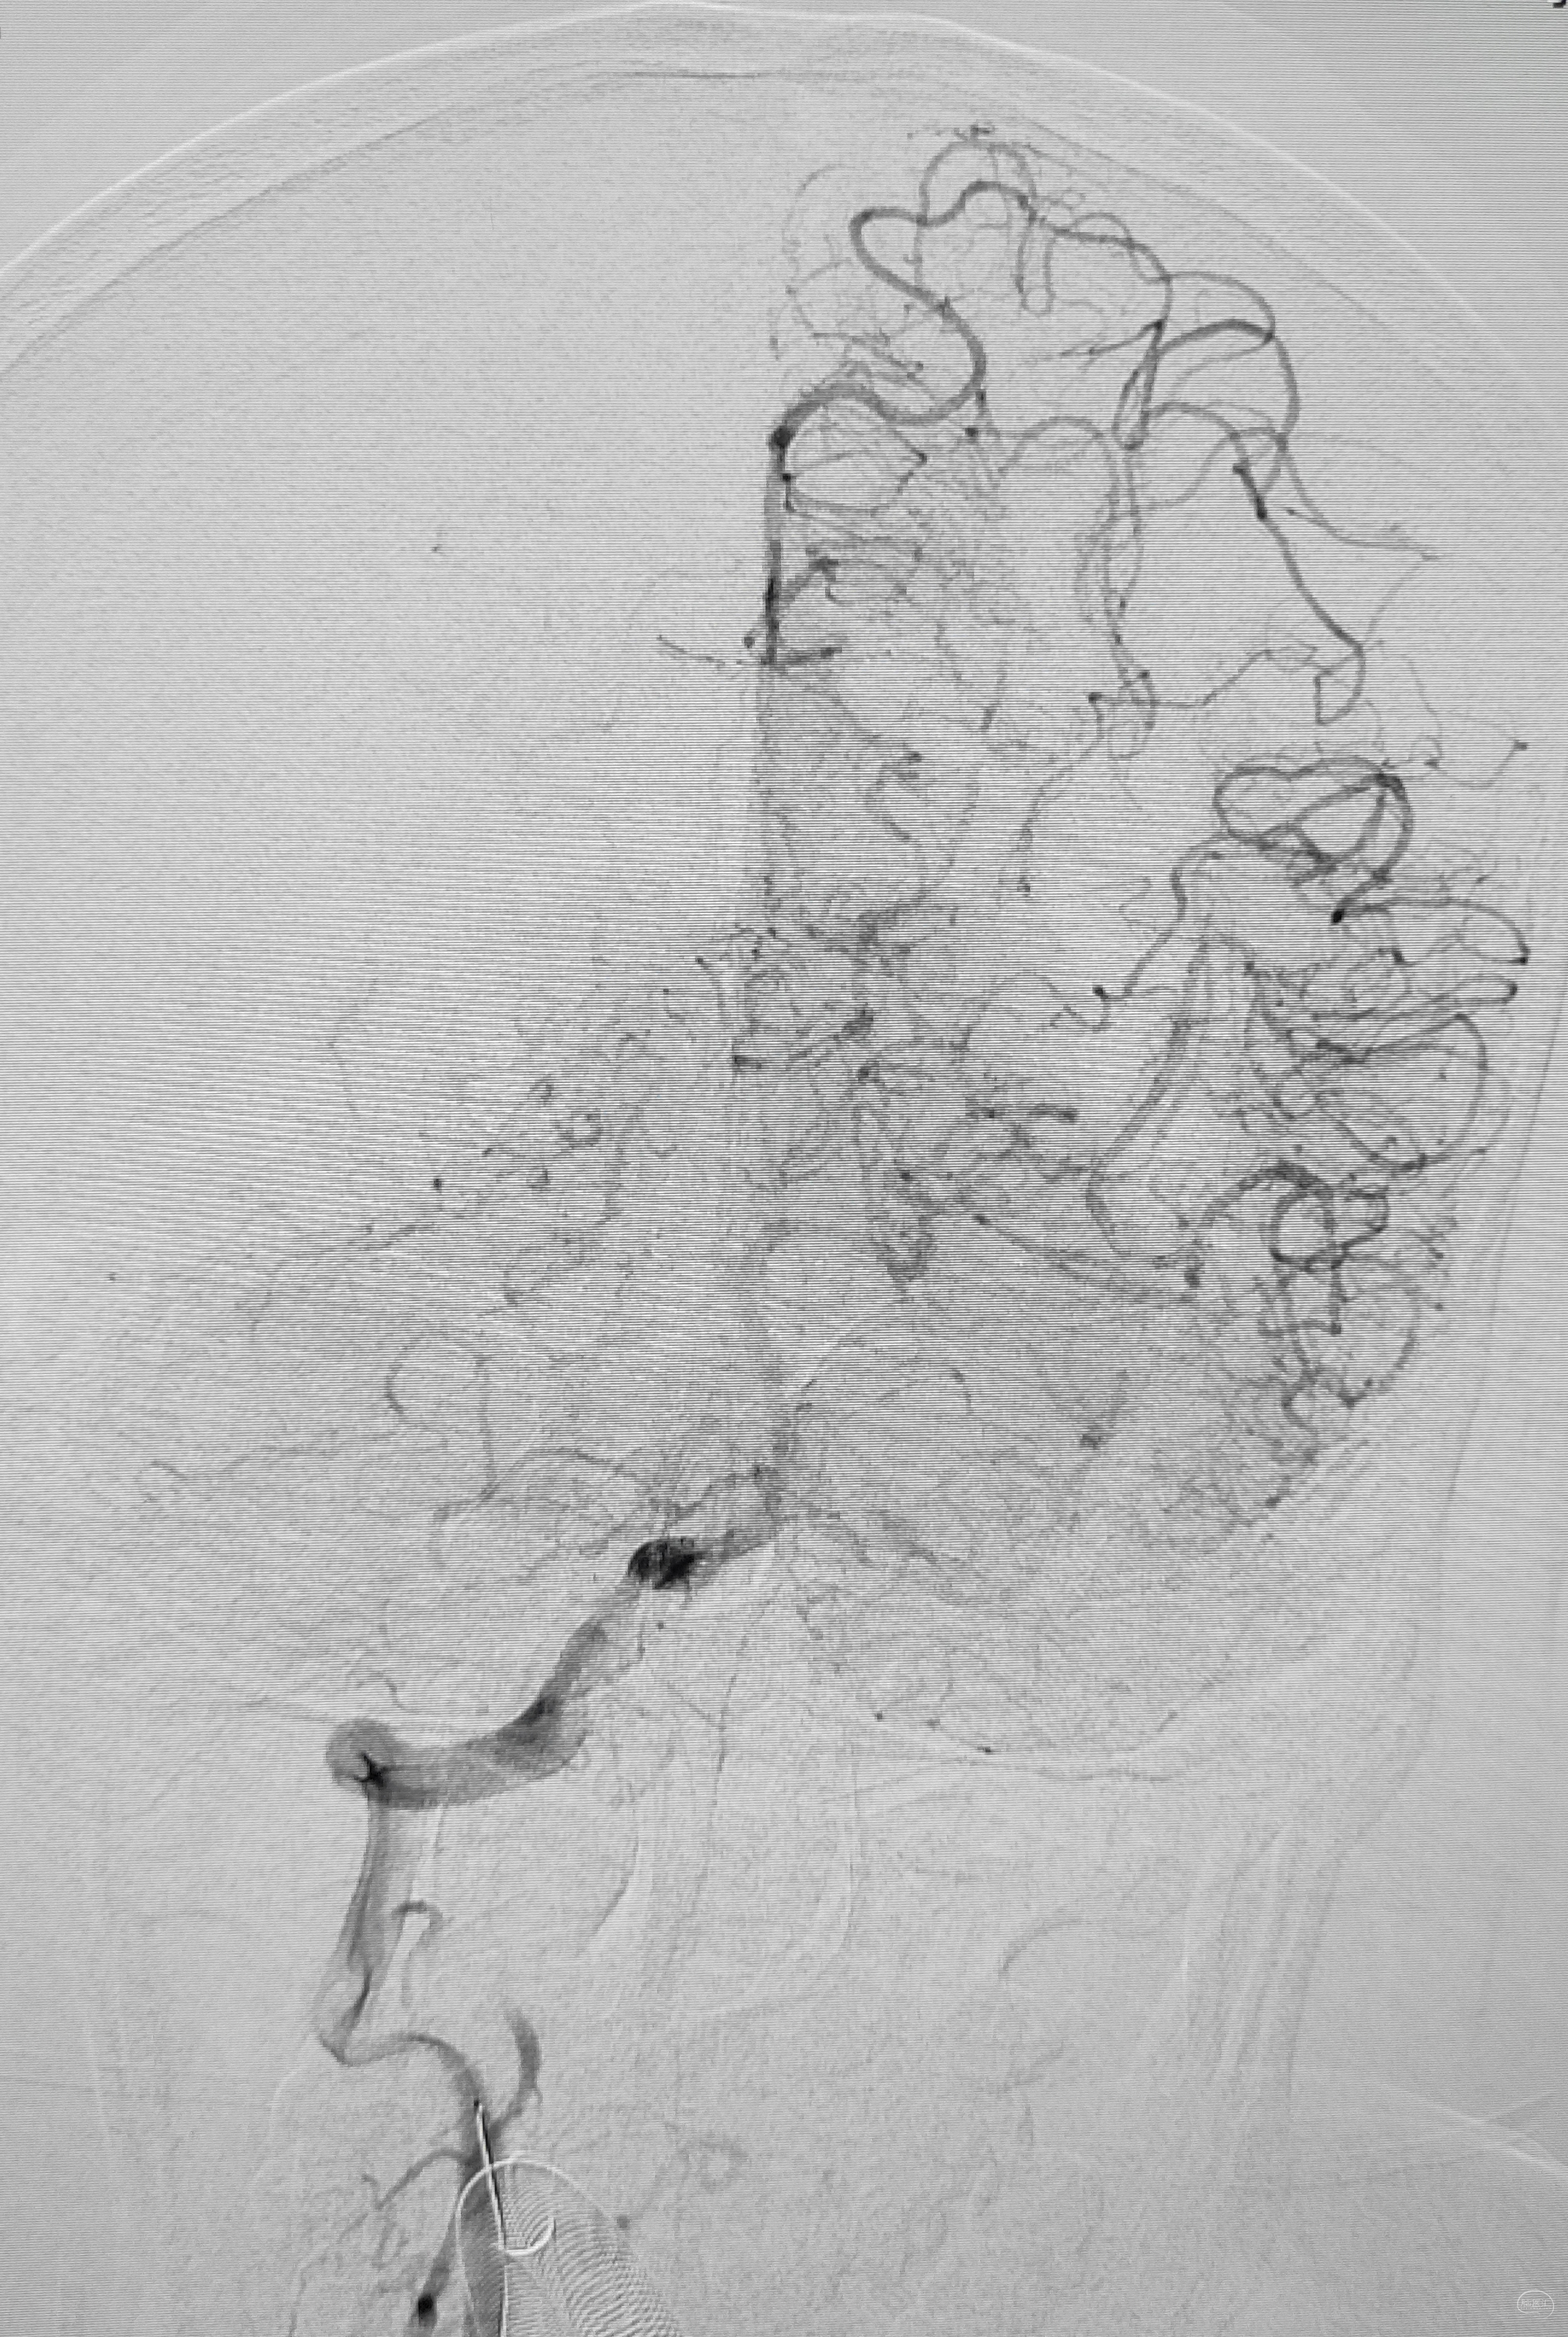

右侧锁骨下造影:右侧椎动脉开口也是重度狭窄,血流速度缓慢,闸门效应明显,此刻,不禁感叹血管的伟大,自己都狭窄得不要不要的了,还努力给对侧代偿供血,奉献精神佳!

右侧颈总动脉正侧位造影:意料之外的是,枕动脉通过肌支与右侧椎动脉吻合(紫色箭头),像极了《大风吹》的歌词“借一杯天上的水”,源源不断进行着血流的补充。但是好景不长,同侧V4段明显狭窄,无情的设置了第二道坎(绿色箭头)。